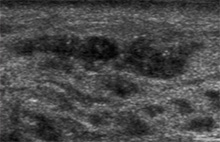

2-3mm 크기의 아주 작은 종괴도 찾아낼 정도로 효율적이나 검사 시간이 많이 소요되고 시술자에 따라 결과 판독의 정확성에 많은 차이가 있으므로 경험 많은 유방 전문 의사에 의해서 시행되어야만 정확한 진단을 내릴 수 있습니다.